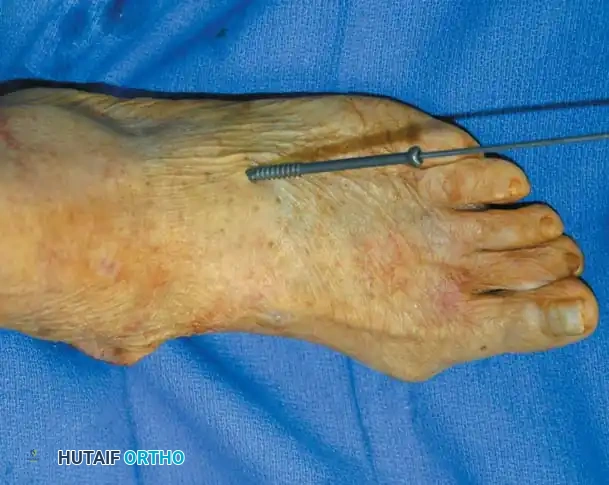

- Fixation: Before closing the dorsal wound over the lesser toe PIP joints, insert 0.054-inch Kirschner wires (K-wires) in a retrograde fashion from the PIP joint distally, then drive them proximally through the proximal phalangeal medullary canal and into the lesser metatarsal remnant.

- Note: K-wires may be omitted if the elliptical incision provides adequate stability and if a painstakingly applied forefoot compression dressing is maintained for 3 weeks postoperatively.

- Closure: Remove the tourniquet and obtain meticulous hemostasis. Close the wounds with nonabsorbable 3-0 suture. Apply a bulky forefoot compression dressing. If K-wires have been used, bend the ends to avoid migration or cover them with commercially supplied protective spheres. Close the plantar skin wound with 3-0 nonabsorbable suture, bringing the metatarsophalangeal (MTP) joints into a neutral or slight flexion position.